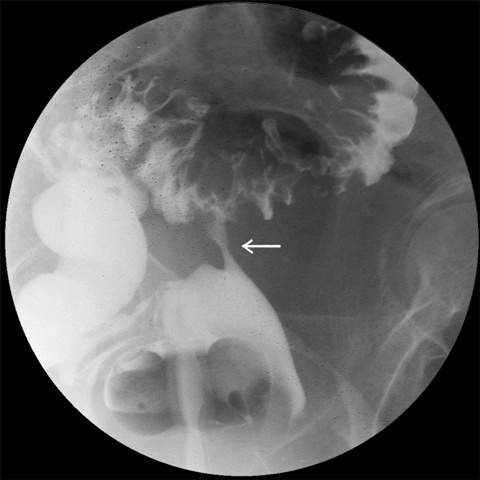

Colovesical fistulas are the most common fistulas associated with diverticular disease. They are more common in men, due to the barrier effect of the uterus in women, but colovesical fistulas can occur in women who have undergone hysterectomies. A one-stage resection with excision of the fistula from the adjacent organ is usually sufficient (Box 2, Box 3).